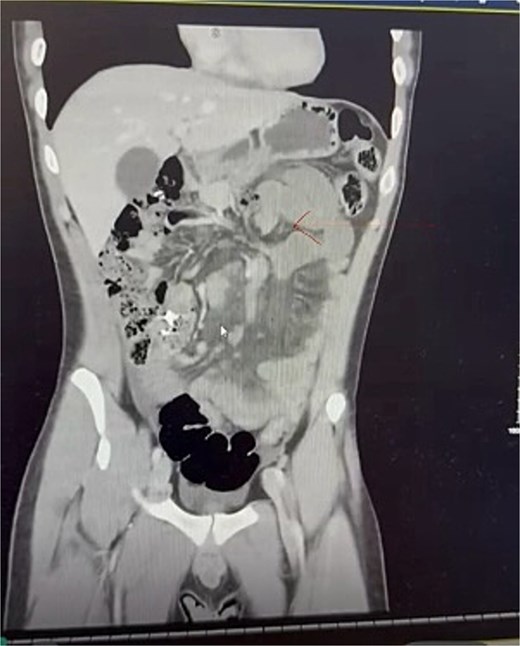

On admission, he was stable. Examination demonstrated normal vital signs, diffuse abdominal tenderness with guarding in the epigastrium. The abdomen was not distended. There were no palpable masses and no peritonitis. Biochemical and haematological parameters revealed a lactate of 2.4 mmol/L and white cell count of 21.6 × 109/L and were otherwise unremarkable. Intravenous (IV) contrast-enhanced computed tomography (CT) of the abdomen and pelvis revealed distended stomach and dilated loops of small bowel with inflammatory change in the mesentery, and an apparent twist in the root of the small bowel mesentery (Fig. 1). A diagnosis of SBO of uncertain aetiology was made.